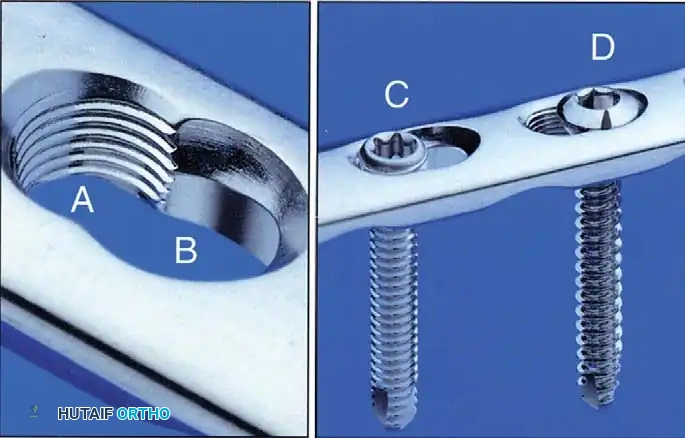

If comminution with bone loss prevents the use of a tension band compression technique—due to the risk of shortening the olecranon and narrowing the greater sigmoid notch—plate fixation is mandatory. Plating is also the gold standard for Monteggia fracture-dislocations, oblique fractures extending distally, and fractures involving the coronoid process.

Construct Design:

Hand-contoured reconstruction plates or modern, anatomically precontoured locking plates (e.g., Acumed, Synthes) provide rigid, stable fixation. The plate is applied to the posterior (tension) surface of the ulna.

Clinical Pearl: When applying a posterior plate, use unicortical screws for the holes immediately adjacent to the articular surface to avoid inadvertent penetration into the radioulnar or ulnohumeral joints.

Fig. 54-58 A-C, Plate fixation can be used to stabilize comminuted fractures of the olecranon. Precontoured plates offer excellent proximal purchase with locking screws. (From Heim U, Pfeiffer KM: Internal fixation of small fractures, 3rd ed, Berlin, 1988, Springer-Verlag.)

🔪 Surgical Technique: Plate Fixation

- Reduction: Restore the articular block. Temporary K-wires can be used to hold comminuted articular fragments.

- Plate Application: Apply a precontoured olecranon plate to the posterior aspect of the proximal ulna. The proximal portion of the plate often wraps over the tip of the olecranon to capture the proximal fragment with multiple locking screws.

- Fixation: Secure the plate distally to the ulnar shaft using standard cortical or locking screws. If an oblique fracture line is present, a lag screw can be placed independently or through the plate to achieve interfragmentary compression.

- Bone Grafting: If significant metaphyseal void exists after elevating impacted articular fragments, autogenous cancellous bone graft or allograft should be packed into the defect prior to final plate tightening.